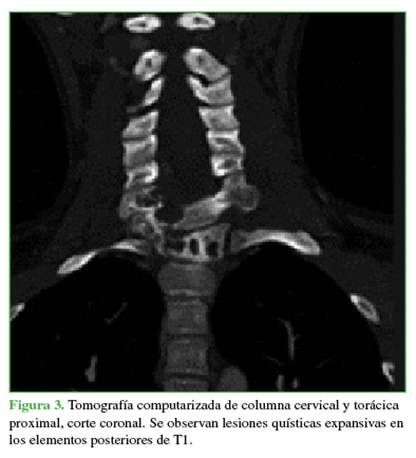

Los estudios complementarios mostraron un compromiso vertebral extenso: en C7 (arco posterior), zonas 4-7 y niveles III y IV de la clasificación de Weinstein-Boriani-Biagini; en T1 (cuerpo vertebral), zonas 10-3 y niveles III y IV; en T2 (pedículo derecho más arco posterior), zonas 3-7, niveles III y IV.11 Las lesiones eran de tipo quística expansiva (Figuras 3 y 4). Ante el patrón expansivo de la lesión, se descartó la sospecha de un hemangioma vertebral. Se interpretó el caso como una lesión con diagnóstico presuntivo de QOA grado 3 de Enneking.

Las radiografías, la tomografía computarizada y la resonancia magnética son los estudios complementarios que ayudan a llegar al diagnóstico. En las radiografías, se observa una cavidad expansiva osteolítica. En la tomografía y la resonancia, se visualizan los característicos niveles líquido/líquido.8